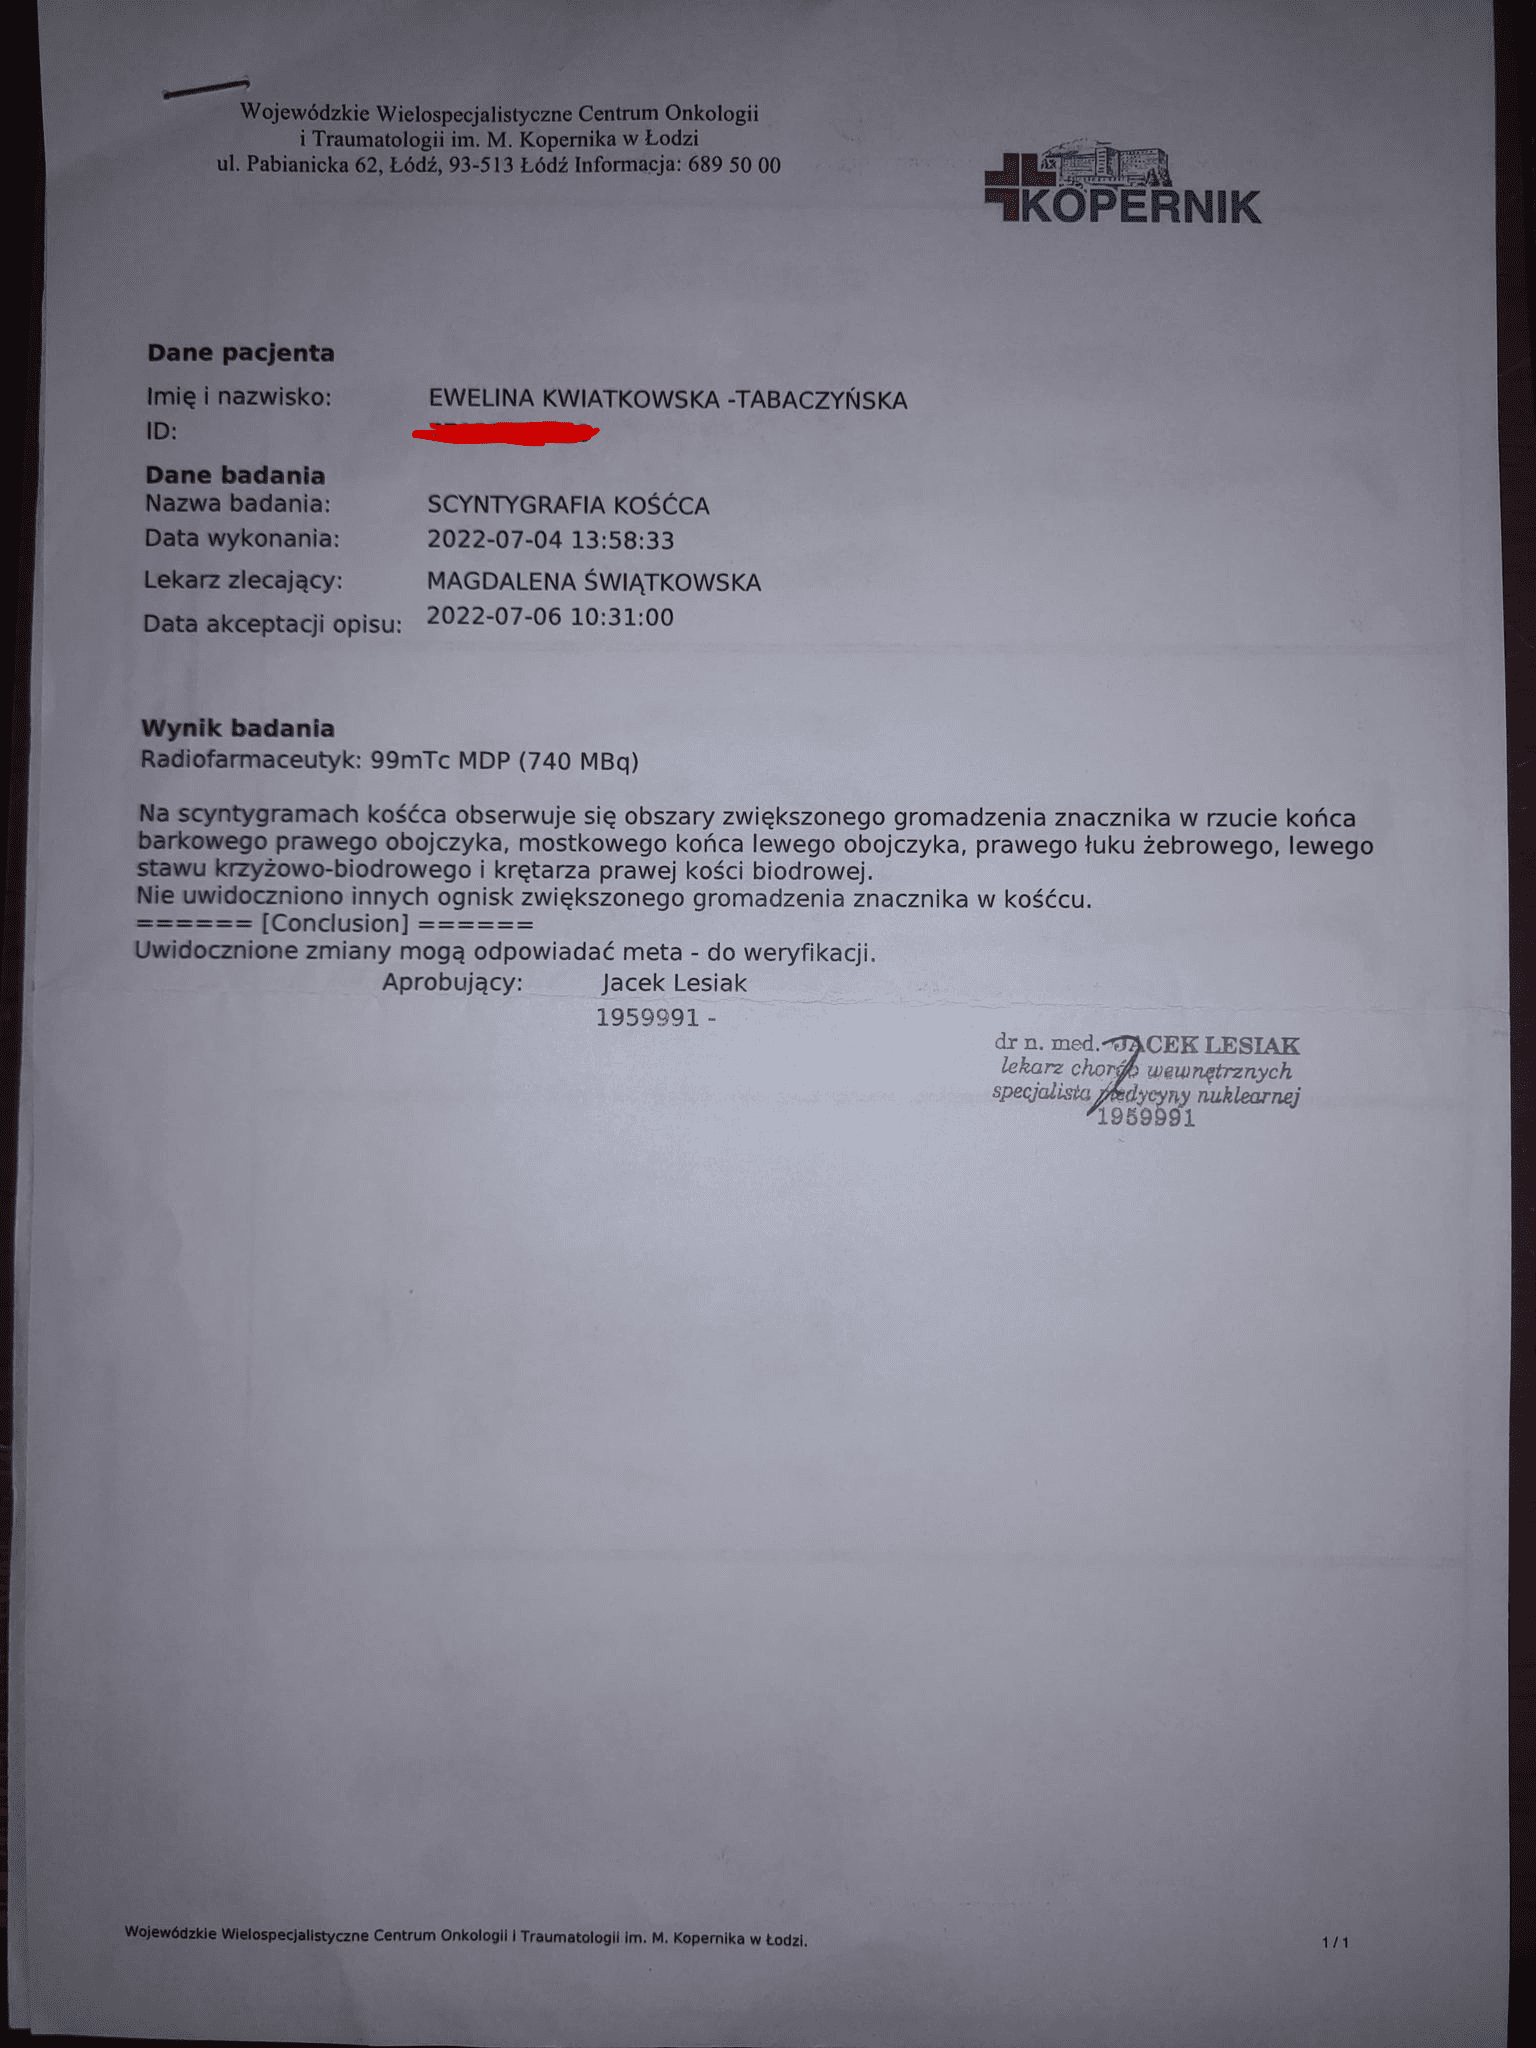

Złośliwy nowotwór piersi, po kolejnych badaniach stwierdzono przerzuty do kości.